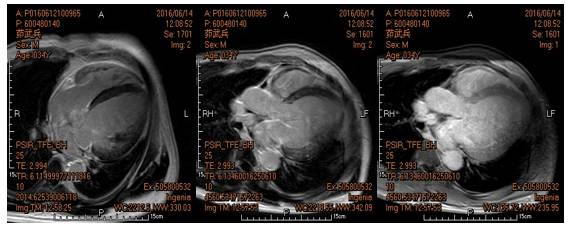

进一步检查:心脏磁共振

左心增大,室间隔心肌中层可疑线状延迟强化

左室侧壁心内膜下可疑延迟强化;轻度二尖瓣关闭不全;心功能不全(LVEF:31%)